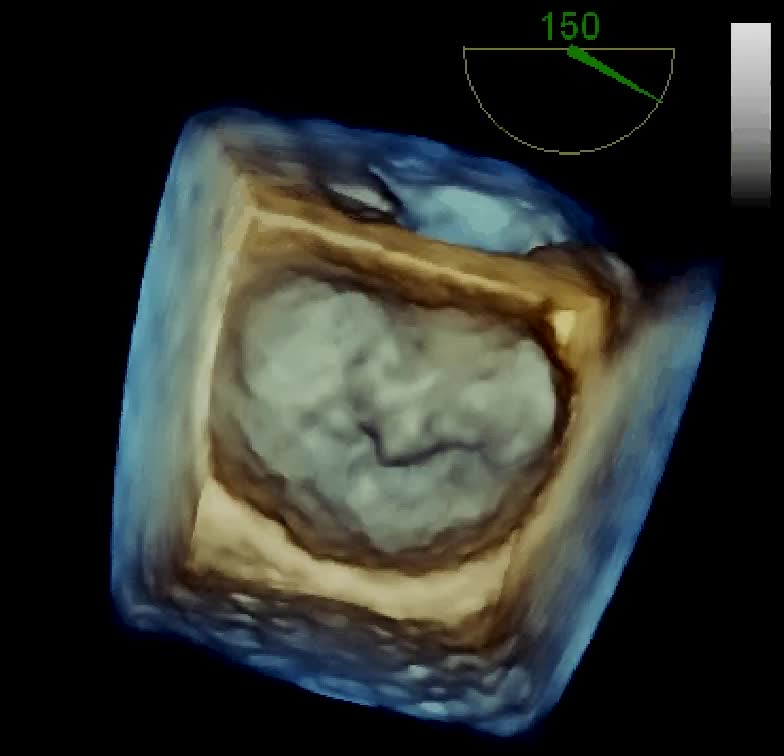

Insufficienza mitralica severa residua dopo recente plastica mitralica

Autore:

Marco Zanobini e Liborio Mammana